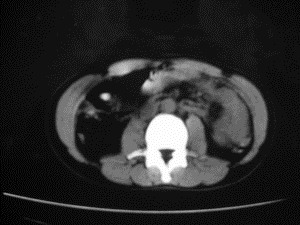

患者女,20岁,被车撞伤3小时,pe:全腹肌紧张,压痛反跳痛,以右上腹为著,肠鸣音减弱。有手术结果。![]() ![]() ![]() ![]() ![]() ![]() ![]() ![]() ![]() ![]() ![]() ![]() ![]() ![]() ![]() ![]() ![]() ![]() ![]() ![]() ![]() jiajie发言: ![]() 考虑空腔脏器穿孔。 dyqct发言:考虑:1、肝左叶外侧段断裂伤伴少量腹血。2、空腔脏器穿孔。 fangzheng发言:仅见腹腔内游离气体,提示空腔脏器穿孔。 guoke发言:胃内密度增高,肠腔内充满气体,考虑肠腔破裂出血 mmg94发言:胃后壁见一增厚软组织密度影,肝左叶前见游离气体影,左腹腔内局部肠管壁、系膜增厚。并见类圆形软组织。以上征象提示消化道管腔破裂,小肠、肠系膜挫裂伤,腹腔血肿形成。 拾荒者发言:肝实质密度不均匀,胃内见不均匀高密度影。考虑:肝挫裂伤,胃内应激性溃疡出血。 守望可可西里发言: 以下是引用jiajie在2006-6-20 15:49:00的发言:[br] [br][br]考虑空腔脏器穿孔。jiajie老师,我鼓起了很大的勇气才决定给您唱个反调儿,如果我错了,请您一定给我指出来,谢谢您了。我反复看了解剖图谱,觉得您所说的“考虑空腔脏器穿孔”上图所用箭头标明的不是游离气体。请您看以下几幅图片: ![]() ![]() ![]() ![]() ![]() ![]() ![]() ![]() 再请您看向医生老师发表的解剖图谱3幅 ![]() ![]() ![]() 这以下几幅图,我认为是肝包膜下积血。不过,说实在话,我没有发现有明显的肝挫裂伤。不对的地方请您一定指出来,再次感谢您了,jiajie 老师! ![]() ![]() ![]() ![]() 这下面几幅图片,我认为有明显的左中上腹部小肠损伤。 ![]() ![]() ![]() ![]() ![]() ![]() ![]() ![]() jiajie 老师,估计我说的是错误的,但我实在闹不明白,请您一定不要笑话我,并指出我的错误,以便于我减少工作中的失误。再次感谢您了,jiajie 老师! 至于胃内的不均匀高密度,我认为拾荒者战友说的有道理,胃内应激性溃疡出血和胃内容物混合所致。 手术结果:左肝叶(iv段)前缘长约8cm挫裂伤口,舌叶根部下< |